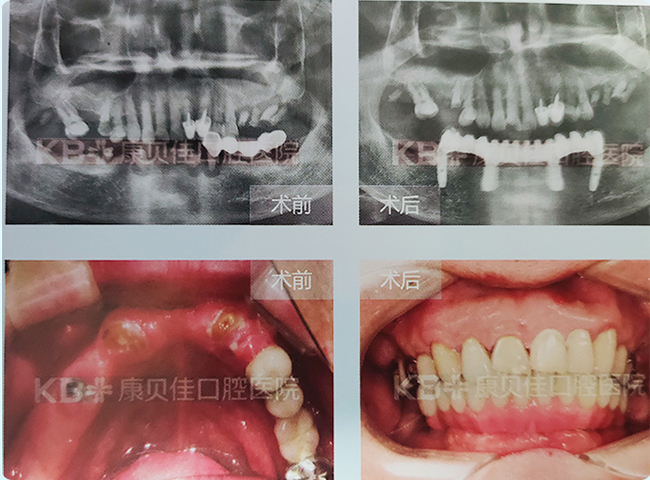

常先生 48岁

上颌右侧两颗牙缺失多年,牙槽骨萎缩严重,无法进行常规种植。到康贝佳采用上颌窦内提升方法,植入和自体血纤维蛋白混合的人工骨粉,然后植入种植体,上愈合基台。戴牙后,非常满意。

治疗方案:

上颌种植2颗